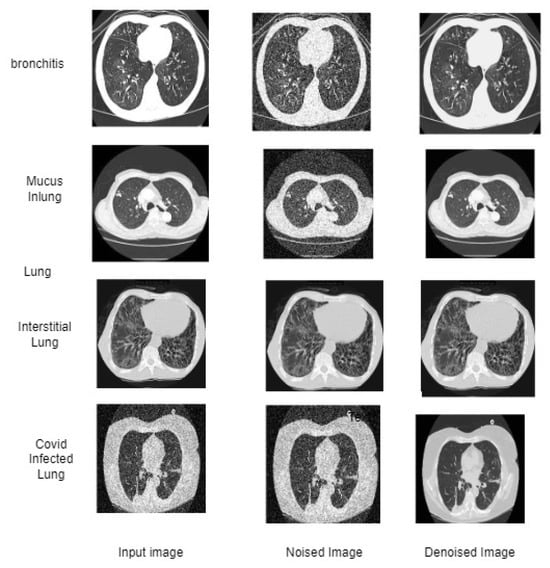

2.4.2. Discussion on Lung CT Images

3.2. Experimental Analysis of ETLFOD Model for Lung CT Dataset